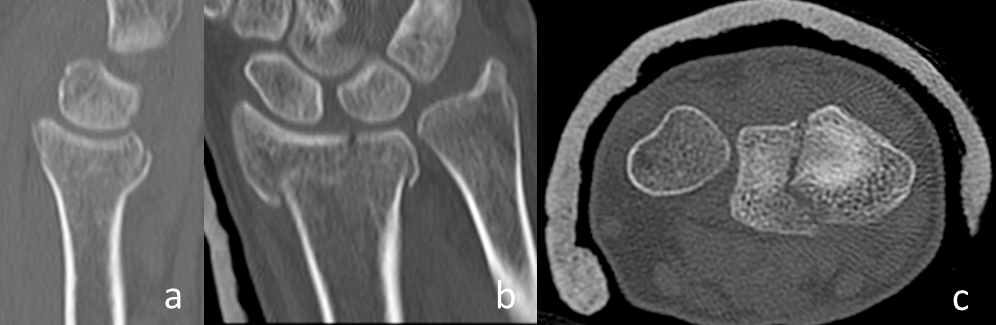

Figure 1: a: The parameter displaced palmar cortex in a conventional sagittal radiograph (circle). b: The parameter displaced frontal split in a sagittal plane of a CT-scan (arrow). c: The parameter displaced sagittal split in a frontal plane of a CT-scan (arrow). The main parameters of the heuristic.

- The displaced frontal split of the articular surface extending dorsally in the metaphysis (Figure 1b [Fig. 1]).

- The displaced sagittal split of the articular surface (Figure 1c [Fig. 1]).

The fact that only displaced fracture parameters have been taken in account for the decision of the surgical approach led to a subgroup of fractures that had paradoxically no palmar cortex and no frontal split as these fracture parameters were not displaced (Figure 3 [Fig. 3]). These fractures did not follow the before mentioned observation. In these cases, the palmar cortex was fractured very far distally and the articular surface was impacted in the metaphysis. We observed 31 of these fractures in our collective: 7 were operated from dorsal, 16 from palmar, and 8 were fractures of the radial styloid process (type B1) that were treated percutaneously.

Figure 3: a: CT in sagittal plane showing the palmar cortex is not displaced. b: CT in frontal pane showing a sagittal split of the articular surface. c: CT in axial plane showing a sagittal split of the articular surface. Distal radius fracture (AO type C2) with a non-displaced palmar cortex (i.e. no palmar cortex) and no frontal split.

The interesting group of “neither palmar cortex nor frontal split fractures” need further evaluation (Figure 3 [Fig. 3]). These fractures are usually not grossly displaced and often amendable to conservative treatment. Their indication for surgery is mainly a dorsal tilt greater than 20 degrees. In these cases, both approaches are feasible: a palmar approach where the tilt is restored with reduction over the plate; a dorsal approach with direct reduction of the impaction. Indirect reduction in these fractures is usually not possible because the joint is impacted in the metaphysis.